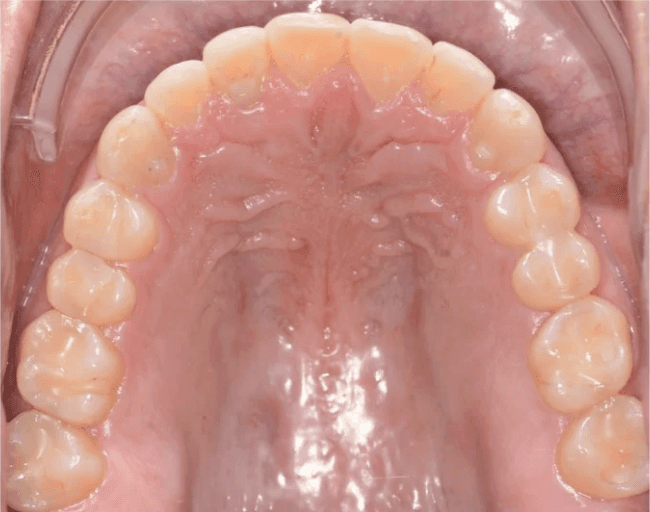

Final results

INTRAORAL